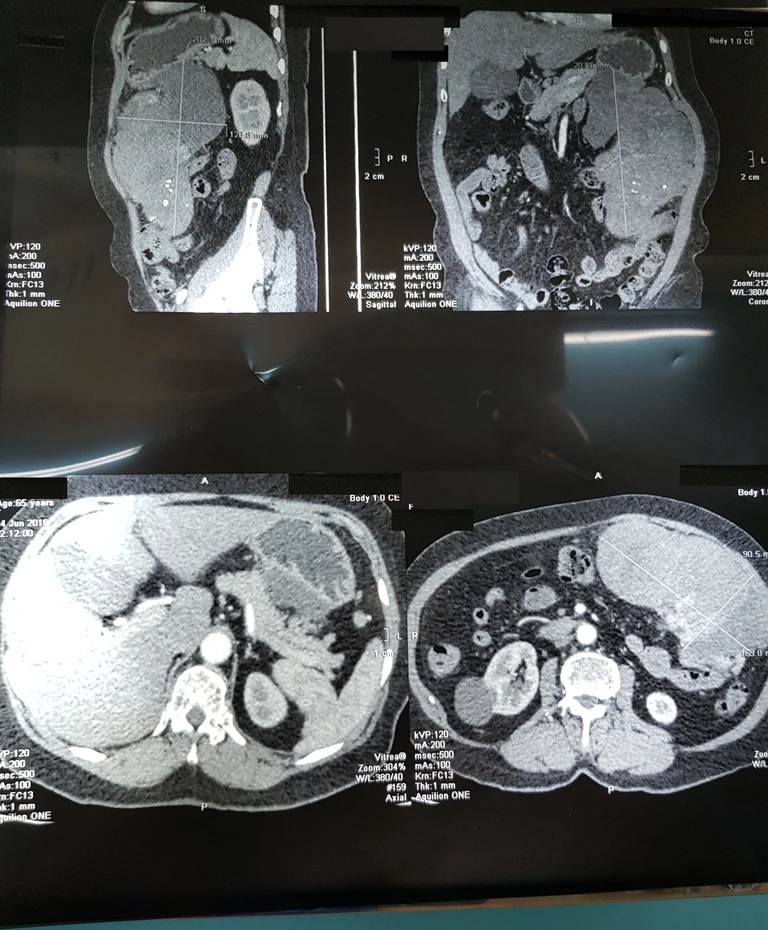

CT-Scan hình ảnh khối bướu rất lớn trong ổ bụng. Ảnh: BVCC